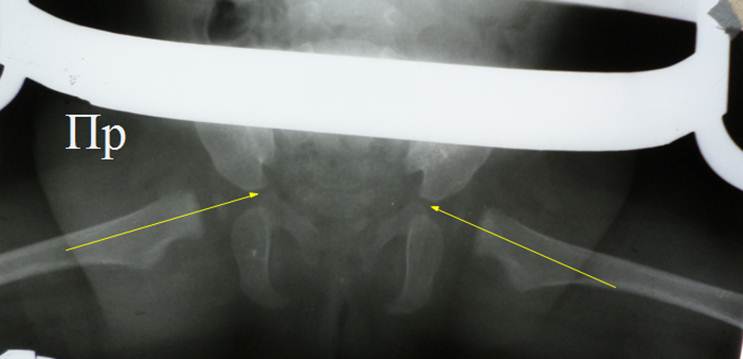

Рентгенограмма

в детском ОТО после госпитализации. Ножки в положении Лоренц I, надеты трусики Фрейка. Очевидна децентрация головок

бедер, несмотря на занятие ножками положения Лоренц I. Оси обеих шеек проходят кнаружи от просвета Y –

образных хрящей. Начато вправление

вытяжением по Мау.

Десятый

день вытяжения по Мау, достигнуто полное

разведение ножек. Контрольная рентгенография

на вытяжении: центрация головок бедер. Оси шеек бедер проходят через

просвет Y – образных

хрящей. Вытяжение снято, наложена

классическая кокситная повязка в положении Лоренц I. Контрольная

рентгенография в гипсе подтвердила сохранение центрации головок бедер.

Предписанный срок носки гипсовой повязки 3 месяца.

Через 3 месяца гипс снят. Возраст ребенка 1 год. Контрольная

рентгенограмма демонстрирует отличный

результат лечения: все рентгенометрические показатели в норме, показатель угла

Виберга значительно опережает возрастную норму. Появились ядра окостенения

головок бедер, размер их одинаковый. Отметим, что повышенные показатели угла

Виберга обычны для детей после лечения в гипсовых повязках, со временем они

входят в возрастную норму. Это никак не отражается на здоровье детей.